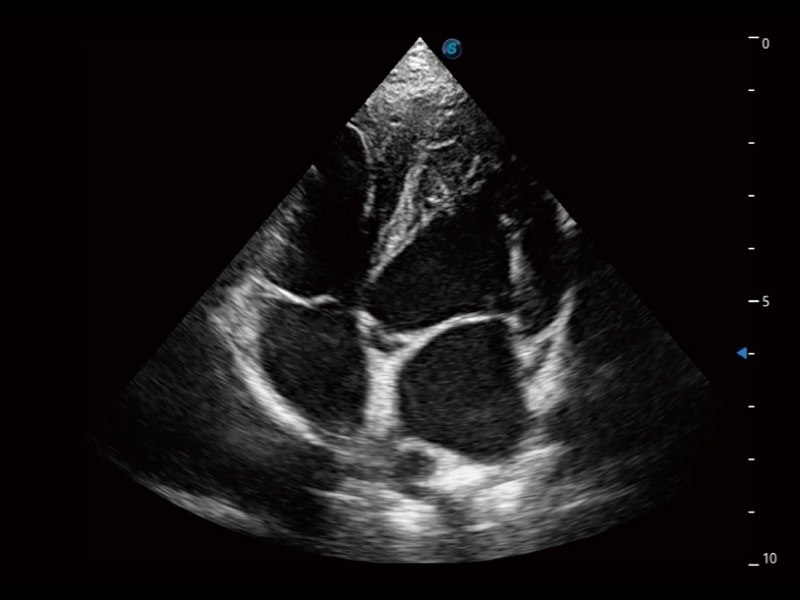

ProPet 70 进一步提升了微米成像算法,更加注重对基础原始图像的还原和保留,在有效减少斑点噪声、增强组织边界显示的同时,避免过度优化丟失真实的解剖信息。

通过360度任意调节3条M型取样线,在同一心动周期上观察心脏不同位置的运动曲线,得到准确的心功能测量数据,有效评估心肌运动及左心室功能。

实时用颜色表示心肌组织运动,观察和定量组织的运动情况,对快速检测与评估心肌的灌注和活性、电传导及心肌收缩和舒张功能等均能提供重要的诊断信息。

ProPet 70专为动物医生设计,对不同的动物体型和生理结构作出了针对性的优化。通过动物影像专用软件,可满足个性化的应用需求,帮助动物医生获得更精确的诊断数据。